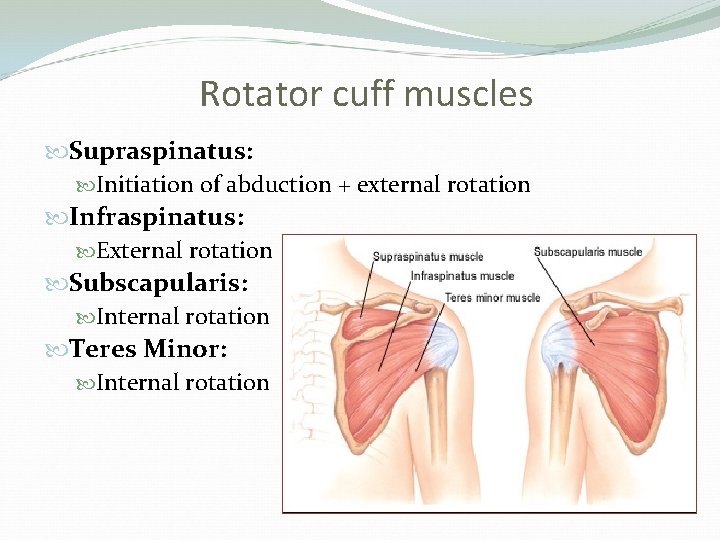

Shoulder anatomy: Rotator cuff muscles Supraspinatus: Abduction Infraspinatus: External rotation Teres Minor: External rotation Subscapularis: Internal rotation

Rotator cuff muscles Supraspinatus: Initiation of abduction + external rotation Infraspinatus: External rotation Subscapularis: Internal rotation Teres Minor: Internal rotation

Cont” Function of rotator cuff muscles Keep the humeral head centered on the glenoid regardless of the arm’s position in space. Generally work to depress the humeral head while powerful deltoid contracts